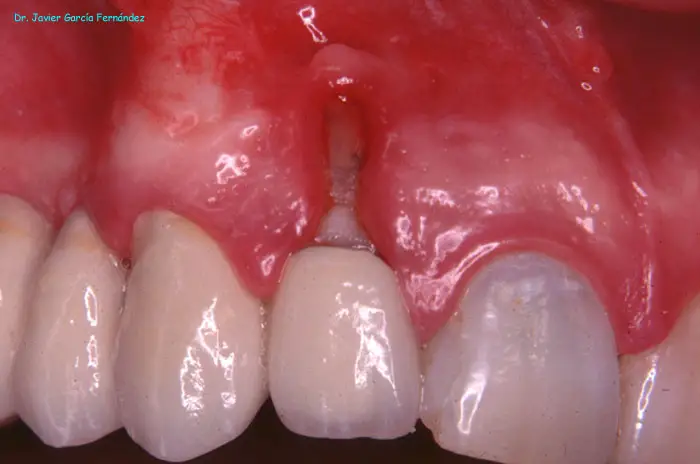

Atlas of Surgical Techniques in Periodontics. Chapter I. Diagnostic of Peridontal Diseases. Classification. Atlas de Técnicas Quirúrgicas en Periodoncia. Cap. I. Classification. Atlas de Técnicas Quirúrgicas en Periodoncia